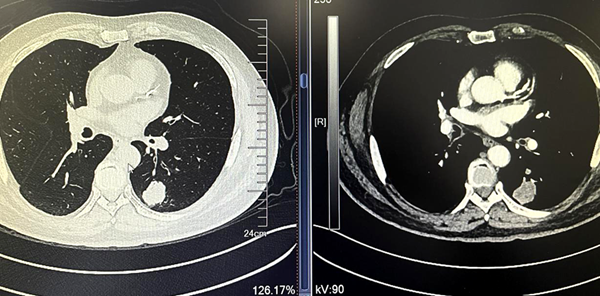

例2:赵某,男,76岁,胸部CT(如下图)示左肺下叶背段占位,不均匀强化,考虑恶性病变,伴多发纵隔淋巴结转移。入院后给予CT引导下经皮肺穿刺活检术。